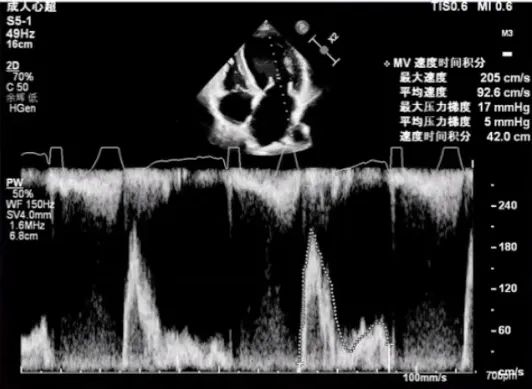

经胸超声评估

经胸超声评估显示,二尖瓣前叶脱垂,并可见广泛反流。

进一步评估患者病变情况,前叶长度2.74mm,后叶长度1.93mm;房间隔前后径4.0cm,房间隔长径6.9cm,瓣口面积6.27cm²,平均跨瓣压差5mmHg。

PG:5mmHg

术前可见肺静脉逆流,术后则消失,反流明显改善。跨瓣压差由术前的19mmHg降至术后8mmHg,瓣膜血流动力学明显优化。同时,LVEDD由术前的6cm逐渐降至<5.0cm,患者左心室容量负荷减轻,心腔重构趋势明确,手术取得良好近期疗效。